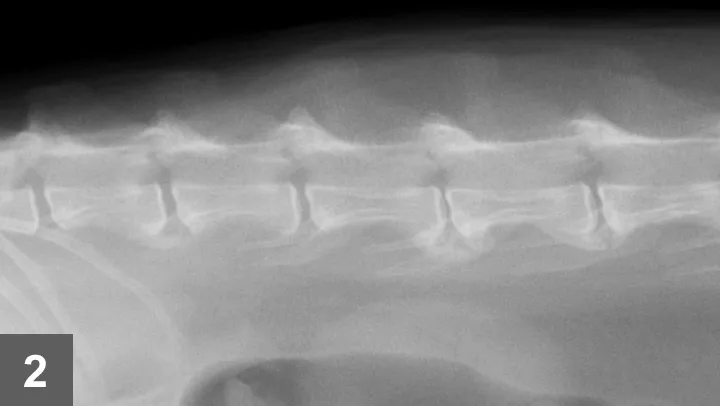

For conclusive proof of osteoarthritis, look for radiographic signs supportive of the loss of articular cartilage, osteophyte formation, bone remodeling, and inflammation along with cytology of joint fluid showing increased inflammatory cell counts and protein levels and decreased viscosity of fluid (see Laboratory Findings/Imaging for further discussion). Spondylosis deformans is diagnosed radiographically by identifying bony spurs of the fibrocartilagenous intervertebral joints of the spine (Figures 1 and 2).

A lateral radiograph of a dog's spine shows a clear view of the vertebral column, highlighting the intervertebral discs and vertebrae. The image allows for assessment of potential abnormalities such as disc herniation or spinal alignment issues.